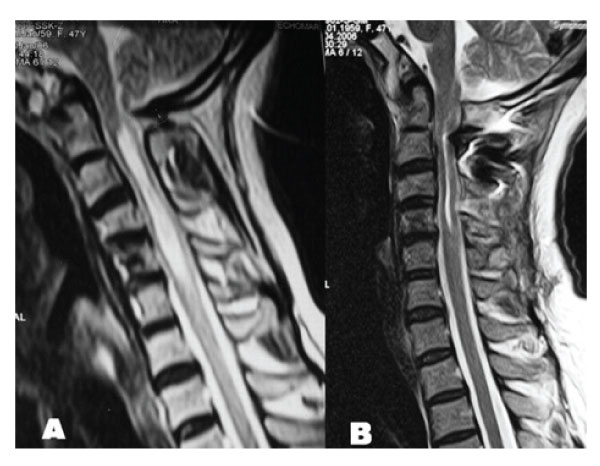

Figure 3: A: T2 weighed sagittal MRI demonstrating cervical syringomyelia without tonsillary herniation. B: Postoperative T2 weighted sagittal MRI demonstrating resolution of cervical syringomyelia.

Antero-posterior diameter of foramen magnum was 20 mm; no bony compression to neural structures including odontoid process was detected, however anterior subarachnoid space could not be seen at the level of brain stem. MR angiography disclosed aplasia of left vertebral artery with a nearly normal trace of the right vertebral artery. The patient was treated by a posterior fossa decompression. In the operation, suboccipital craniectomy was performed. The right lamina of the atlas was also removed. Dural surface became expanded and pulsatile suggesting foramen magnum stenosis. CSF flow was observed after opening the dura mater. A large duraplasty was made with dural graft to maintain the CSF flow. Following the decompression and large duraplasty, occipital cervical fusion using C2 laminar screwing was performed. Post-operative period was uneventful, spasticity and weakness of the extremities and hyperreflexia improved. MR examination obtained six months after the operation showed the resolution of the syringomyelia [Figure 3,4].